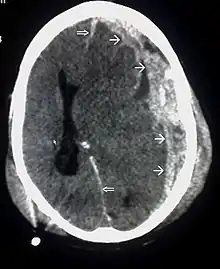

CT scan showing epidural hematoma (arrow)

Diagnosis is suspected based on lesion circumstances and clinical evidence, most prominently a neurological examination, for example checking whether the pupils constrict normally in response to light and assigning a Glasgow Coma Score.[23] Neuroimaging helps in determining the diagnosis and prognosis and in deciding what treatments to give.[75] DSM-5 can be utilized to diagnose TBI and its psychiatric sequelae.[76][77][78]

The preferred radiologic test in the emergency setting is computed tomography (CT): it is quick, accurate, and widely available.[79] Follow-up CT scans may be performed later to determine whether the injury has progressed.[10]